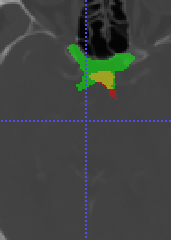

In Chapter 6, we propose an end-to-end, atlas-free 3D convolutional deep learning framework for fast and fully automated whole-volume HaN anatomy segmentation [115]. Our deep learning model, called AnatomyNet, segments OARs from head and neck CT images in an end-to-end fashion, receiving whole-volume HaN CT images as input and generating masks of all OARs of interest in one shot. AnatomyNet is built upon the popular 3D U-net architecture, but extends it in three important ways: 1) a new encoding scheme to allow auto-segmentation on whole-volume CT images instead of local patches or subsets of slices, 2) incorporating 3D squeeze-and-excitation residual blocks in encoding layers for better feature representation, and 3) a new loss function combining Dice scores and focal loss to facilitate the training of the neural model. These features are designed to address two main challenges in deep-learning-based HaN segmentation: a) segmenting small anatomies (i.e., optic chiasm and optic nerves) occupying only a few slices, and b) training with inconsistent data annotations with missing ground truth for some anatomical structures. We collect 261 HaN CT images to train AnatomyNet, and use MICCAI Head and Neck Auto Segmentation Challenge 2015 as a benchmark dataset to evaluate the performance of AnatomyNet. The objective is to segment nine anatomies: brain stem, chiasm, mandible, optic nerve left, optic nerve right, parotid gland left, parotid gland right, submandibular gland left, and submandibular gland right. Compared to previous state-of-the-art results from the MICCAI 2015 competition, AnatomyNet increases Dice similarity coefficient by 3.3% on average. AnatomyNet takes about 0.12 seconds to fully segment a head and neck CT image of dimension , significantly faster than previous methods. In addition, the model is able to process whole-volume CT images and delineate all OARs in one pass, requiring little pre- or post-processing. We demonstrate that our proposed model can improve segmentation accuracy and simplify the auto-segmentation pipeline. These contributions are released as an open-source software package called AnatomyNet, which is publicly available555https://github.com/wentaozhu/AnatomyNet-for-anatomical-segmentation. Portions of this chapter were published as part of [115].

- [121] W. Zhu and X. Xie. Adversarial deep structural networks for mammographic mass segmentation. arXiv:1612.05970, 2016.